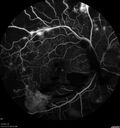

49 year old man with vision loss in the right eye for 2 weeks. VA 20/40 OD, 20/63 OS. DM x 15 years and HTN.